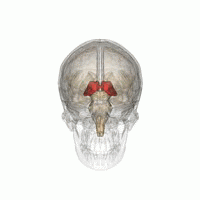

Тала́мус, иногда — зри́тельные бугры (лат. thalamus; от др.-греч. θάλαμος «комната, камера, отсек») — отдел головного мозга, представляющий собой большую массу серого вещества, расположенную в верхней части таламической области промежуточного мозга хордовых животных, в том числе и человека. Впервые описан древнеримским врачом и анатомом Галеном. Таламус — это парная структура, состоящая из двух половинок, симметричных относительно межполушарной плоскости. Таламус находится глубже структур большого мозга, в частности коры или плаща. Под таламусом расположены структуры среднего мозга. Срединная (медиальная) поверхность обеих половинок таламуса одновременно является верхней боковой стенкой третьего желудочка головного мозга[1][2][3].

Таламус расположен вблизи центра мозга и входит в число структур таламической области промежуточного мозга. Он залегает под структурами большого мозга, но возвышается над структурами среднего мозга. Восходящие аксоны, исходящие из нейронов ядер таламуса, формируют пучки миелинизированных нервных волокон. Эти пучки нервных волокон обильно проецируются на различные области коры больших полушарий головного мозга во всех направлениях. Медиальная поверхность обеих половинок таламуса одновременно является верхней частью боковой стенки третьего желудочка головного мозга. Она соединена с соответствующей медиальной поверхностью противоположной половинки таламуса плоской полосой белого вещества. Эта полоса представляет собой пучок миелинизированных нервных волокон и называется межталамическим сращением, или промежуточной массой третьего желудочка, или срединной комиссурой (срединной спайкой) таламуса.

Таламус состоит из нескольких отдельных областей серого вещества. Эти области представляют собой группы таламических ядер, разделённых областями белого вещества. Белое вещество, разделяющее и облегающее отдельные таламические ядра и группы ядер, представляет собой пучки миелинизированных нервных волокон. Кроме того, в таламусе выделяют также особые группы нейронов, отличающихся по своему гистологическому строению и биохимическому составу от остальной части таламуса, такие, как перивентрикулярное ядро, внутрипластинчатые ядра, так называемое ограниченное ядро и другие[3]. Эти отличающиеся по своей гистологической структуре и биохимическому составу от остальных ядер таламуса особенные ядра обычно группируют в так называемый аллоталамус, в противоположность «типичным» таламическим ядрам, которые группируют в так называемый изоталамус[7].

Ядра таламуса на основании особенностей их анатомо-гистологической структуры и цитоархитектоники можно подразделить на шесть групп: передние, медиальные, боковые, ретикулярные, внутрипластинчатые ядра и ядра средней линии. Тонкий Y-образный слой миелинизированных нервных волокон, так называемая внутренняя мозговая пластинка, разграничивает между собой переднюю, срединную и боковую группы таламических ядер. У человека передняя и срединная группы таламических ядер содержат всего по одному большому ядру, называемому соответственно передним дорсальным и медиальным дорсальным ядрами таламуса. Между тем боковая группа ядер таламуса человека подразделяется на дорсальный и вентральный уровни. Дорсальный уровень боковых ядер таламуса человека состоит из бокового дорсального, бокового заднего ядер и ядер подушки таламуса. Вентральный уровень боковых ядер таламуса человека, в свою очередь, состоит из вентрального переднего, вентрального бокового, вентрального задне-бокового и вентральных задних медиальных ядер[8].